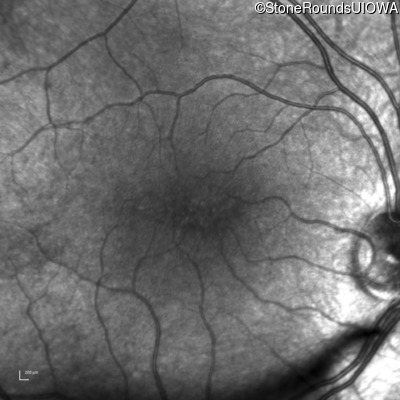

Infrared Fundus Photograph - Right - 20/40 -2

Exemplar